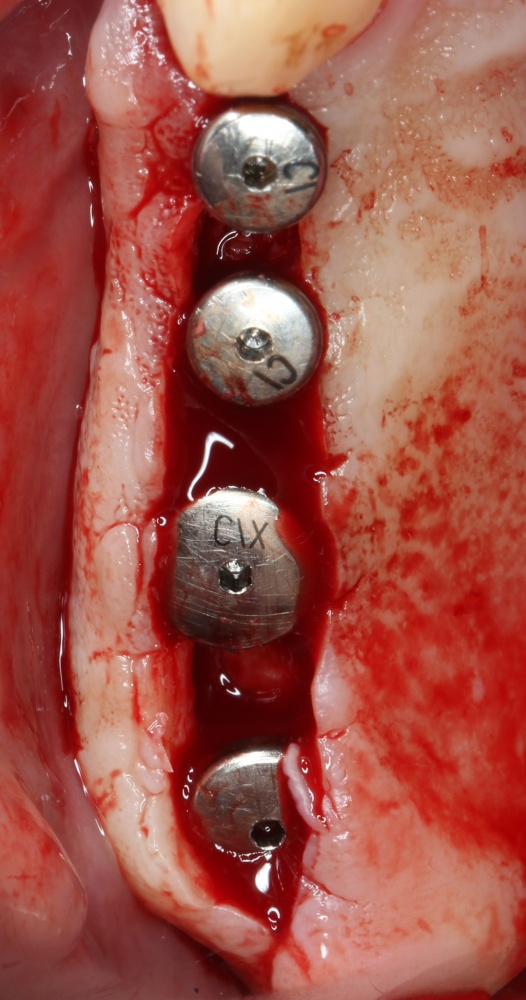

1. С имплантатами или без имплантатов?

В 2007 году, когда я сделал первую в своей жизни операцию синуслифтинга, мой тогдашний наставник требовал от меня строгого выполнения правила: «Если расстояние до дна гайморовой пазухи 6 мм и менее — мы делаем синуслифтинг отдельным этапом. Если больше — можно сочетать синуслифтинг с установкой имплантатов.»

С тех пор прошло много лет, и сейчас мы смело ставим имплантаты одновременно с синуслифтингом, если расстояние до дна верхнечелюстной бухты составляет от 1-2 мм, а для 6 миллиметров толщины кости  используем имплантаты длиной 8-9 мм, вообще обходясь без синуслифтинга (см. совет выше).

Следовательно, если имплантат, при соблюдении хирургического протокола и правил позиционирования, устойчив в слое кости толщиной 2 мм, то его можно поставить одновременно с операцией синуслифтинга:

А если нет, то нельзя.

Например, имплантаты Nobel Replace, Dentium, Xive прекрасно стабилизируются в миллиметровом слое костной ткани. В то же время Nobel Active, Ankylos или Bicon не совсем подходят для таких условий. Конечно, это не значит, их нельзя установить в двухмиллиметровом слое кости одновременно с синуслифтингом, но риск возникновения проблем многократно возрастает.

Например, как на картинках выше — безусловно, мы можем использовать субкрестальные имплантаты одновременно с синуслифтингом и пытаться стабилизировать их в двухмиллиметровом слое костной ткани. И, возможно, в некоторых случаях получим хороший результат (см. когда повезло). Однако, намного чаще из-за неправильного подбора имплантатов возникают проблемы, перерастающие в ошибки, которые потом приходится долго и тяжело исправлять.